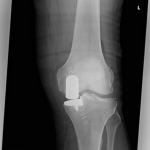

PRACHATICE – Na ortopedickém oddělení Nemocnice Prachatice byl minulý týden proveden unikátní výkon – implantace oboustranné částečné náhrady kolenního kloubu. Jde o málo frekventovaný typ operace, který se provádí jen na menším počtu ortoepedických pracovišť v České republice.

Unikondylární náhrada představuje šetrnější variantu totální endoprotézy – nahrazuje pouze poškozenou část kolenního kloubu, zatímco zbytek zůstává zachován. Aby pacient z operace skutečně profitoval, je nutné splnění indikačních kritérií, která lze shrnout do několika bodů: artrotické postižení jedné poloviny kloubu a dobrý stav té druhé, funkční vazy, dobrý rozsah pohybu, nepřítomnost výrazné deformity.

S oboustrannými implantacemi totálních endoprotéz mají v prachatické nemocnici již několikaleté zkušenosti. Nyní však poprvé provedli dvojitou operaci částečné náhrady. Zásadní je přitom nejen zvládnutá operační technika, ale i souhra celého týmu, díky které je pacient schopen se již v prvních hodinách po výkonu postavit, operované klouby zatížit a relativně bezbolestně zvládat rehabilitaci.